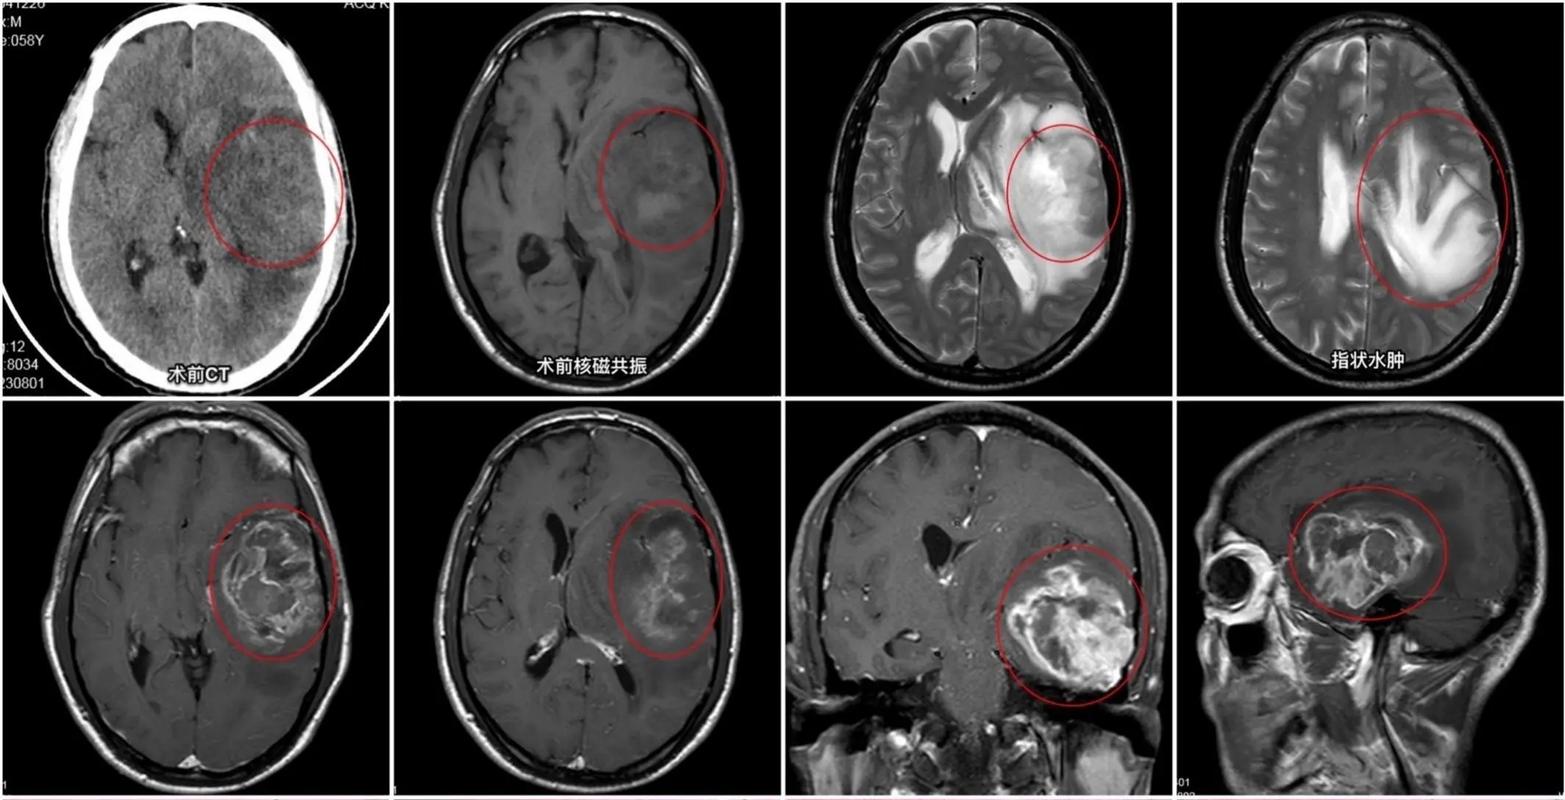

- 头颅CT(计算机断层扫描):最快、最基础的检查,可以快速判断是否有脑出血、大面积脑梗塞、肿瘤占位效应和颅骨骨折,但对于小的胶质瘤和早期脑梗,CT可能不敏感。

- 头颅MRI(磁共振成像):这是诊断脑部疾病的金标准,MRI能非常清晰地显示脑肿瘤的位置、大小、与周围脑组织的关系,以及脑梗塞的范围和时期,对于怀疑胶质瘤的患者,MRI是必须做的。